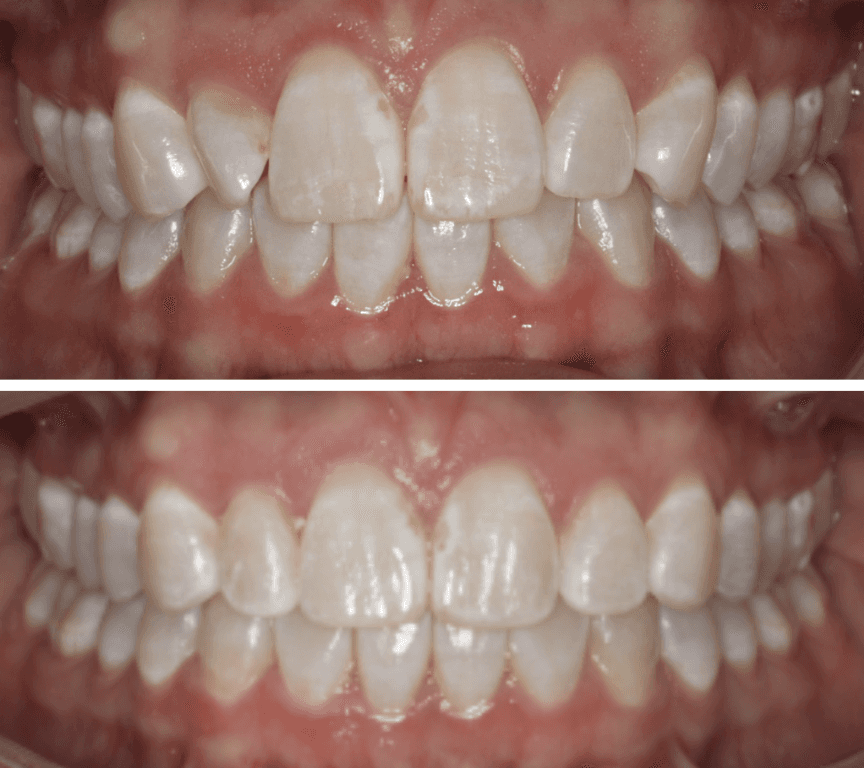

Diagnosis: Deep bite, lower anterior crowding, rotated upper lateral, arch misalignment, wear on teeth from grinding

Adjuncts: Attachments, IPR

Initial treatment

Final results

INTRAORAL